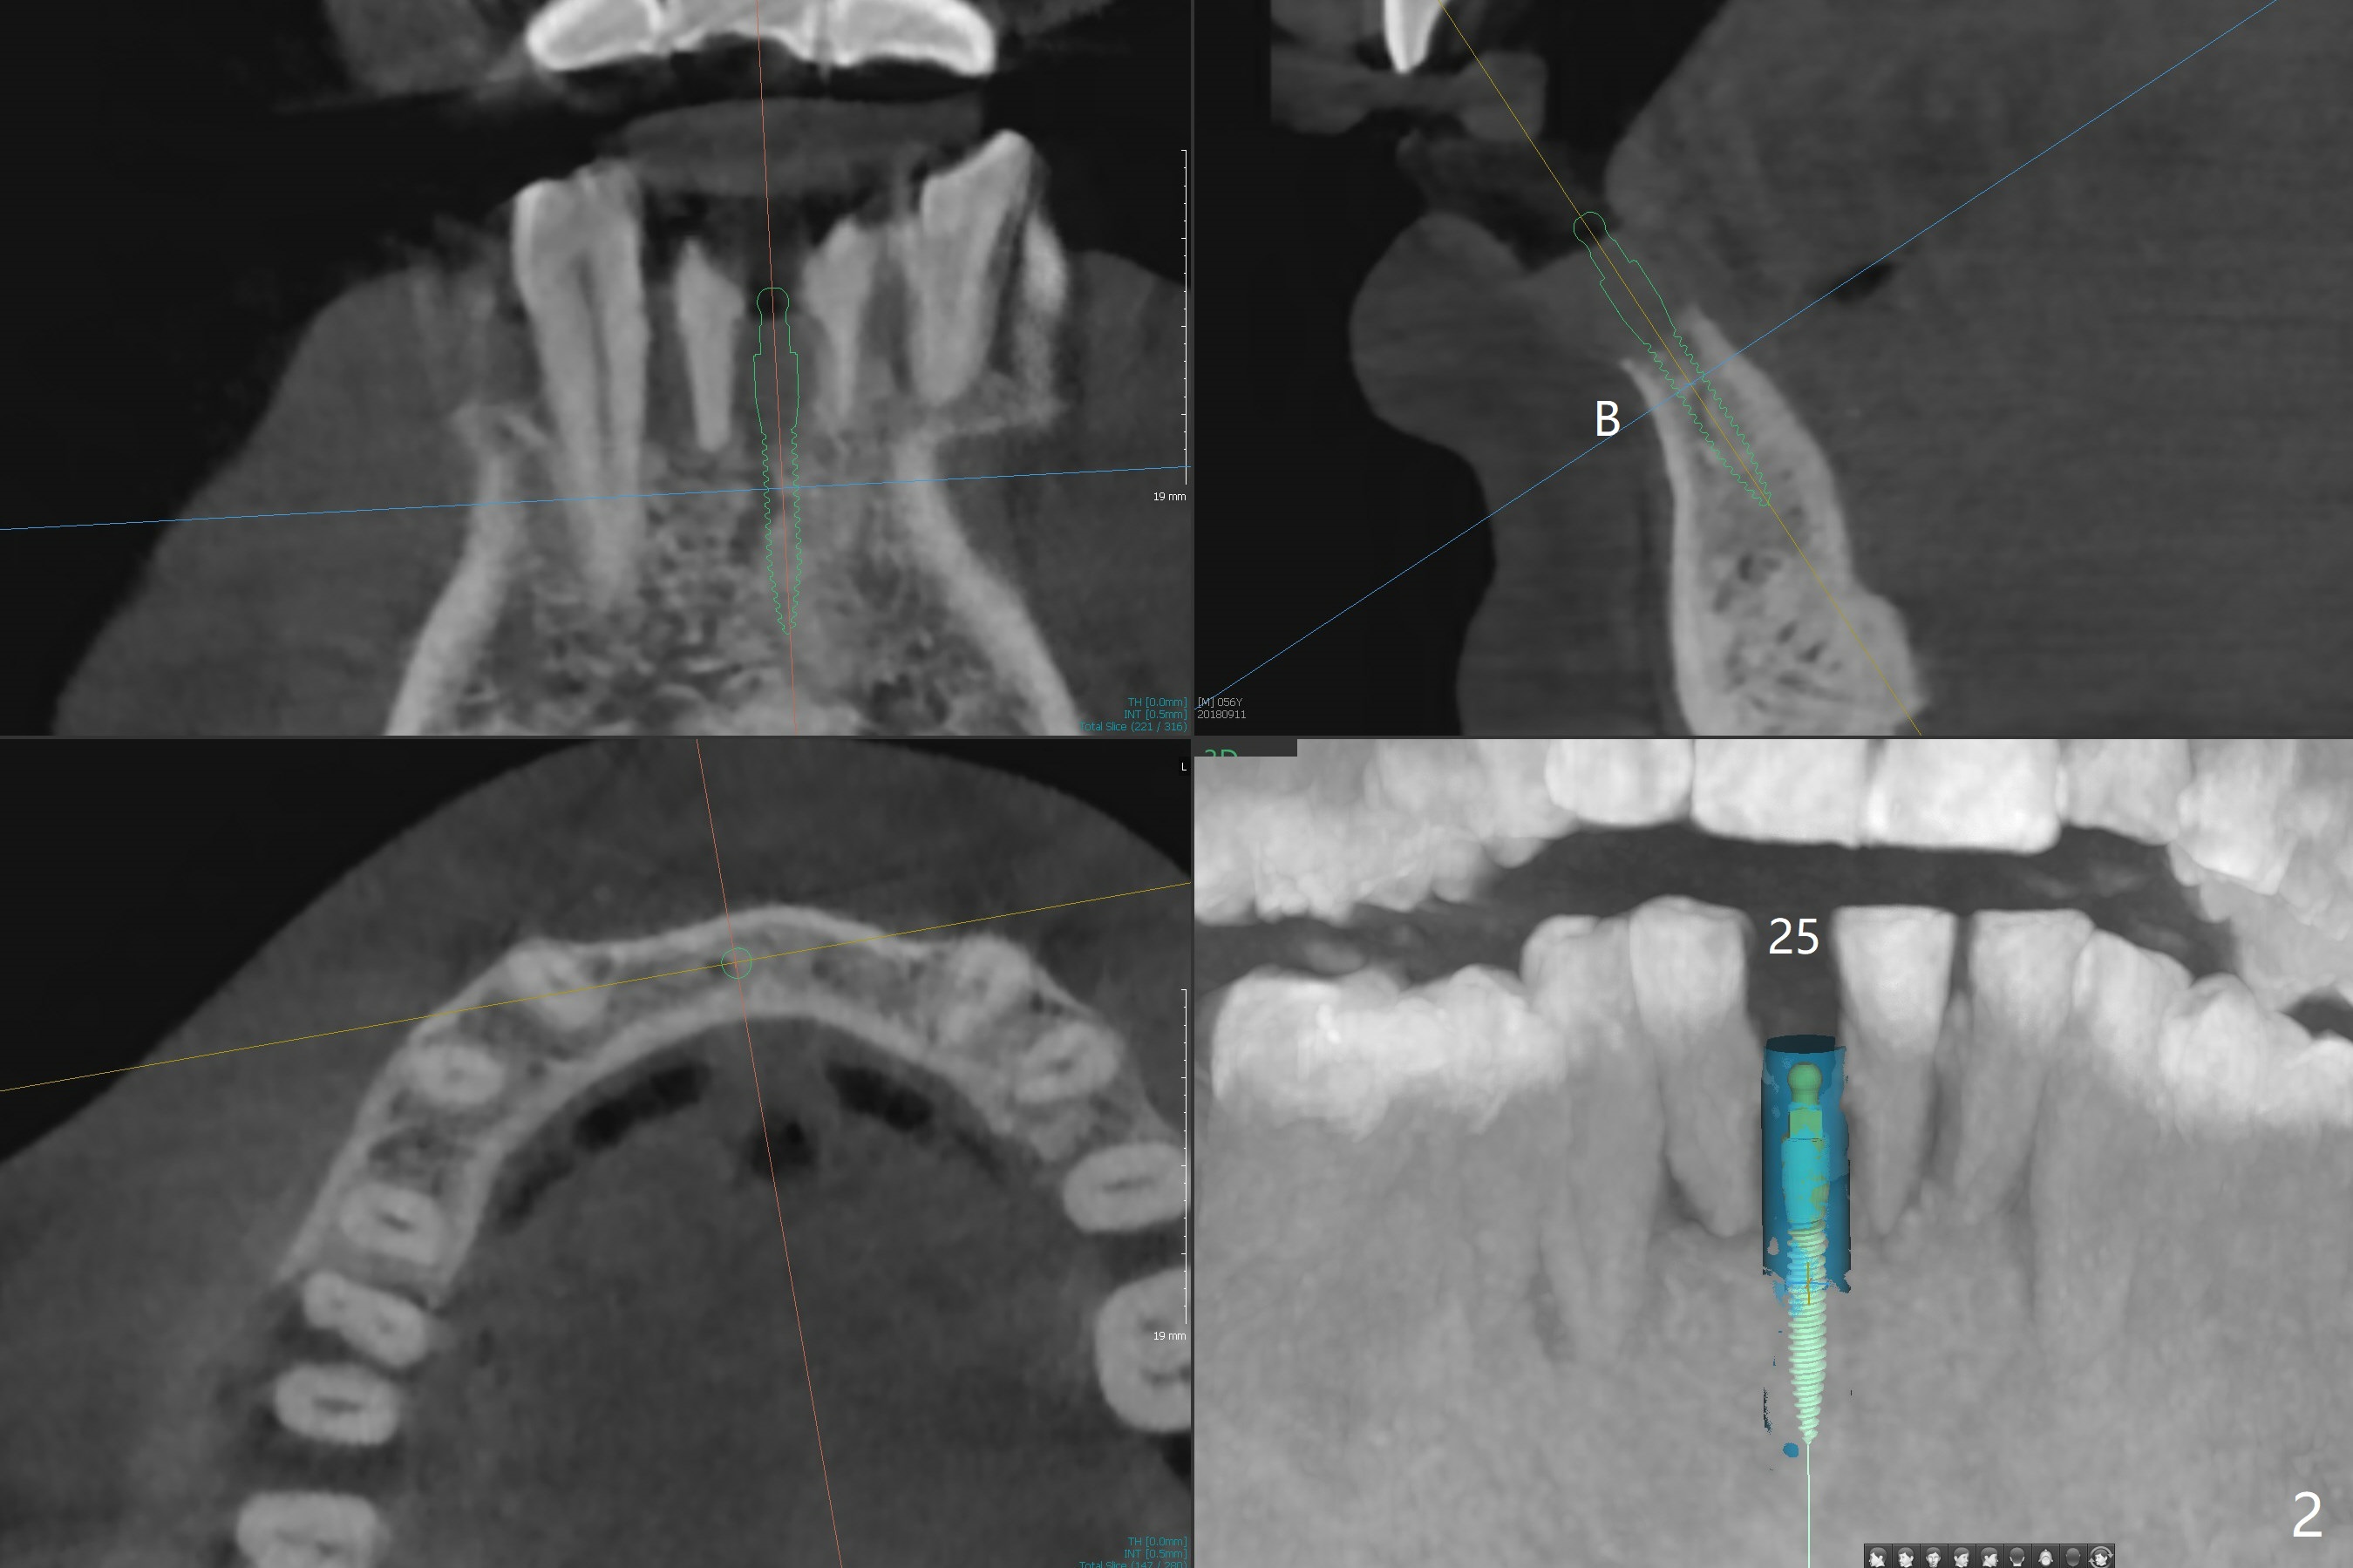

A 56-year-old man is a dental phobic. He finally seeks treatment because of loss of the tooth #25 with air leakage during speech (Fig.1). If the remaining lower incisors are stable after scaling and root planing, a 2.5 or 2.0 mm 1-piece implant will be placed in the narrow edentulous space (Fig.2). The implant driver (green sleeve) may touch the neighboring teeth, which need adjustment. If the worst incisor (#26 tender prior to SRP) is deemed to be non-salvageable, a 2.5 mm implant will be placed with a cantilever 2-unit FPD (Fig.3). If the tooth #23 is a survivor, two of 2.5 or 2.0 implants will be placed at #24 and 26 with a subsequent FPD (Fig.4). If the remaining incisors are all questionable in prognosis, two implants will be placed in the ends with a FPD (Fig.5). After SRP, the tooth #26 is less tender; the patient is ok with its extraction, but insists on saving #23 and 24. If 2 implants are to be placed at #25 and 26, they need to be 2 mm in diameter (Fig.6) with risks of injuring the neighboring teeth. It appears that it is more reasonable to have a single implant, slightly larger (2.5 or 3 mm), at #26, with the coronal end slightly mesial (Fig.7) with a cantilever bridge. If the teeth #23 and 24 fail in the future, a normal one will be easily converted.